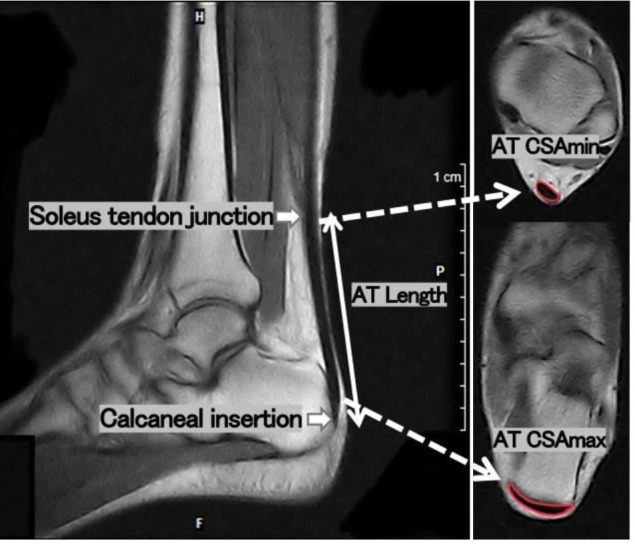

Methods: Ten male and ten female trained university Kendo players participated in the study. Magnetic resonance imaging was used to capture images of the sagittal and transverse images of the AT, from which the transverse cross-sectional area (CSA), length, and volume were calculated. AT stiffness was also assessed using the MyotonPRO, and rebound jump and single-leg hop performance were measured.